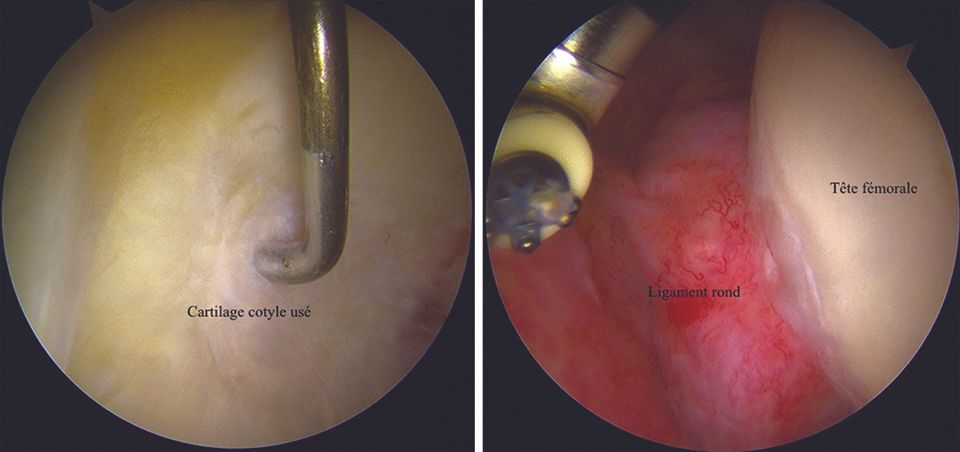

3, 4. Central views

In the central quadrant, the exploration covers the floor of the acetabulum, the round ligament and part of the femoral head (Fig. 10).

5. Posteroinferior view

This view allows the exploration of the inferior cartilaginous part of the acetabulum, the transverse ligament and its junction with the posterior portion of the labrum, and a part of the femoral head (Fig. 11).

6. Femoral head view

This view enables the exploration of a large part, but not all, of the cartilage of the femoral head (Fig. 12).